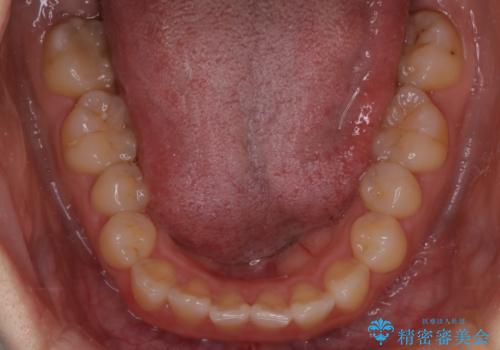

【インビザライン】前歯のがたつきを目立たない装置で治療

- 前歯の叢生を主訴に来院されました。目立たない装置を希望されたためインビザラインで治療を行いました。

IPRと拡大をし、叢生を治しました。右上2番は反対咬合でしたが短期間できれいに治りました。